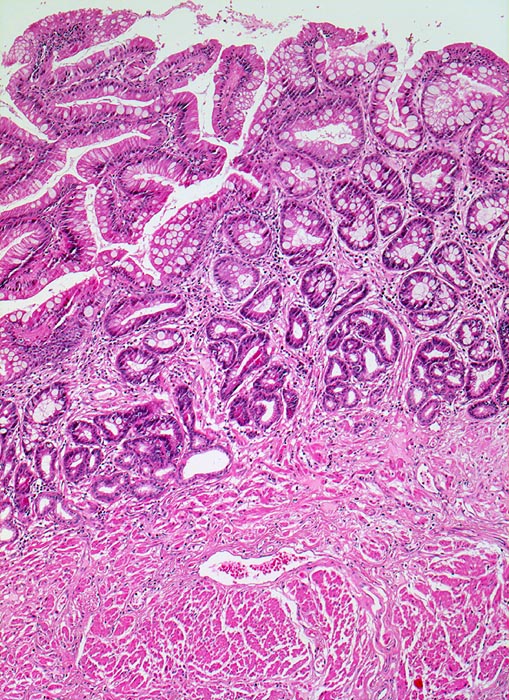

Makroskopisch finden sich zungenförmige, nach proximal reichende rötliche (lachsfarbene), der Magenschleimhaut ähnliche Schleimhautausläufer im distalen Ösophagus. Die Barrettmukosa ist charakterisiert durch eine intestinalen Metaplasie mit Becherzellen (> 9) innerhalb des metaplastischen Zylinderepithels des distalen Ösophagus.

Zusätzlich kann die Barrettmukosa eine niedriggradige (> 3) oder hochgradige intraepitheliale Neoplasie (=Dysplasie) mit zunehmenden zellulären und architektonischen Atypien entwickeln und schliesslich in ein invasives Adenokarzinom übergehen. Die Verwechslung mit reaktiven entzündlich bedingten Atypien führt oftmals zur Überdiagnose einer niedriggradigen Dysplasie.

• Distales Ösophagusteilstück.

• Von oben nach unten: Magenschleimhaut vom Fundustyp mit spezialisierten Magendrüsen, Ösophagusschleimhaut (nicht verhornendes Plattenepithel), Schleimhaut vom Kardiatyp (villoglanduläre Oberfläche, Zylinderzellen) mit herdförmig intestinaler Metaplasie (Becherzellen und Paneth'sche Körnerzellen mit rotem granulärem Zytoplasma) vereinbar mit Barrettmukosa.

• Keine Epitheldysplasie (intraepitheliale Neoplasie) im Bereich der Barrettmetaplasie.